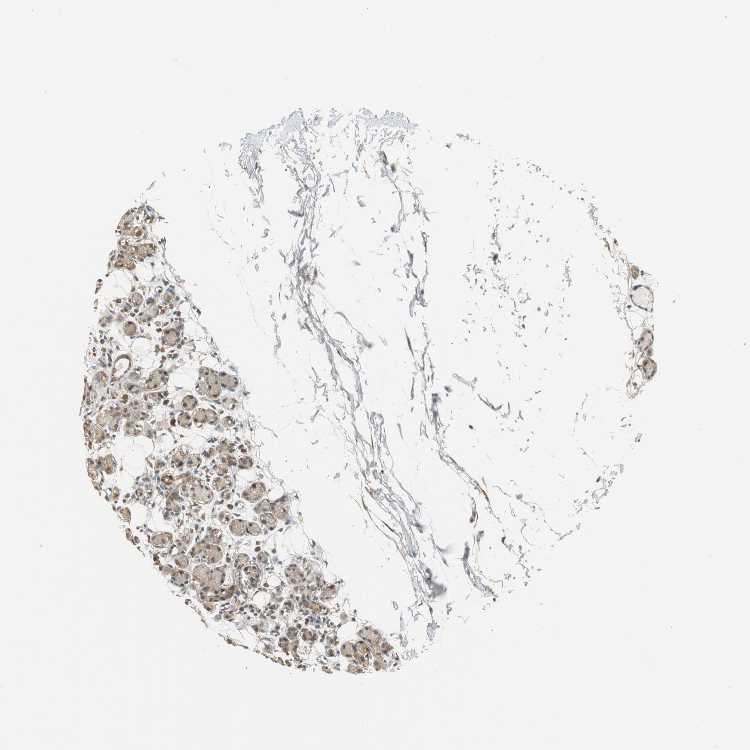

SOFT TISSUE 1 - Antibody stainingi

Antibody staining in the annotated cell types in the current human tissue is reported as not detected, low, medium, or high, based on conventional immunohistochemistry profiling in selected tissues. This score is based on the combination of the staining intensity and fraction of stained cells.

Each image is clickable and will lead to virtual microscopy that enables deeper exploration of all samples and also displays staining intensity scores, fraction scores and subcellular localization as well as patient and tissue information for each sample.

Antibody HPA006431

Fibroblasts Medium